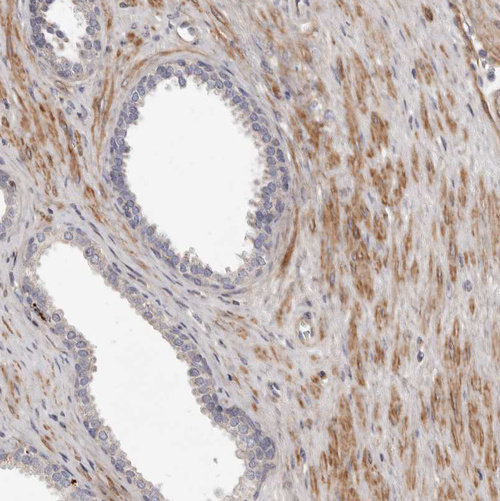

Immunohistochemical staining of human skeletal muscle shows strong cytoplasmic positivity in myocytes.